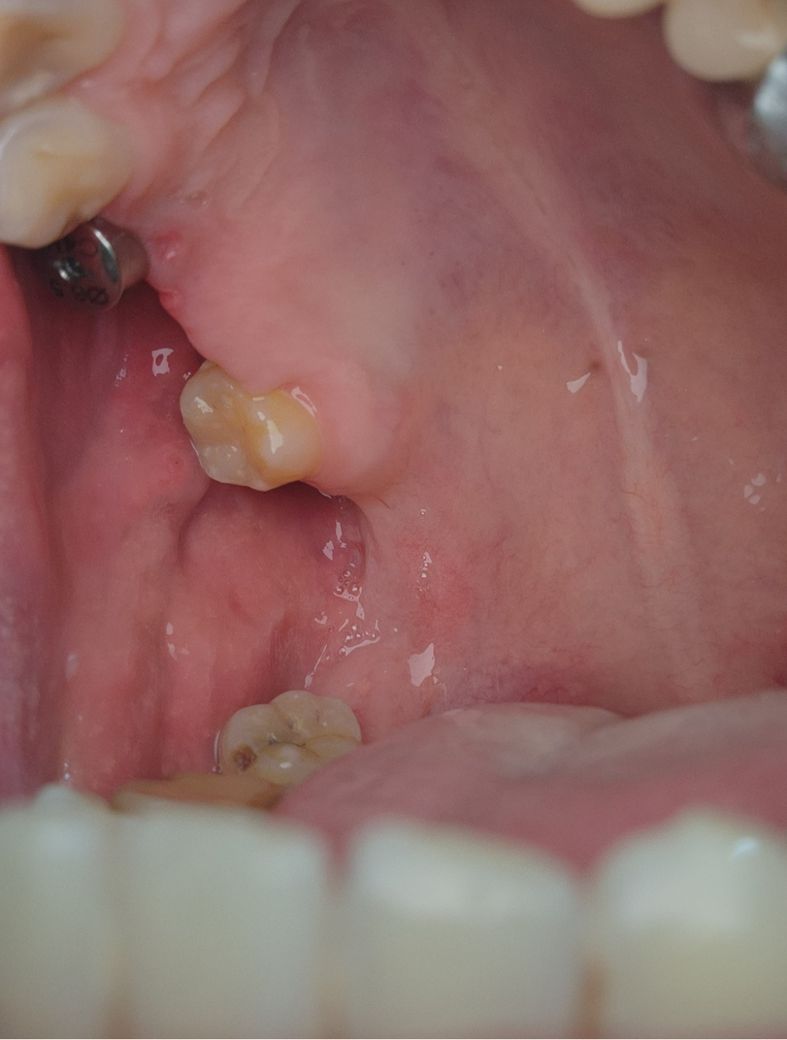

임플란트식립 부위 잇몸에 염증이 생긴것으로 보입니다. 원인은 치석이 쌓여 잇몸을 자극하였을 가능성도 있으며, 방치시에 잇몸염증이 악화되어 임플란트 식립에도 문제를 주기에 빠른 시일내에 치과 치료가 필요로 됩니다.

임플란트 심으신데 염증이 생겨서 잇몸이 많이 내려간거 같은데 치과에 가셔서 검진을 받아보시는게 좋을것같습니다.